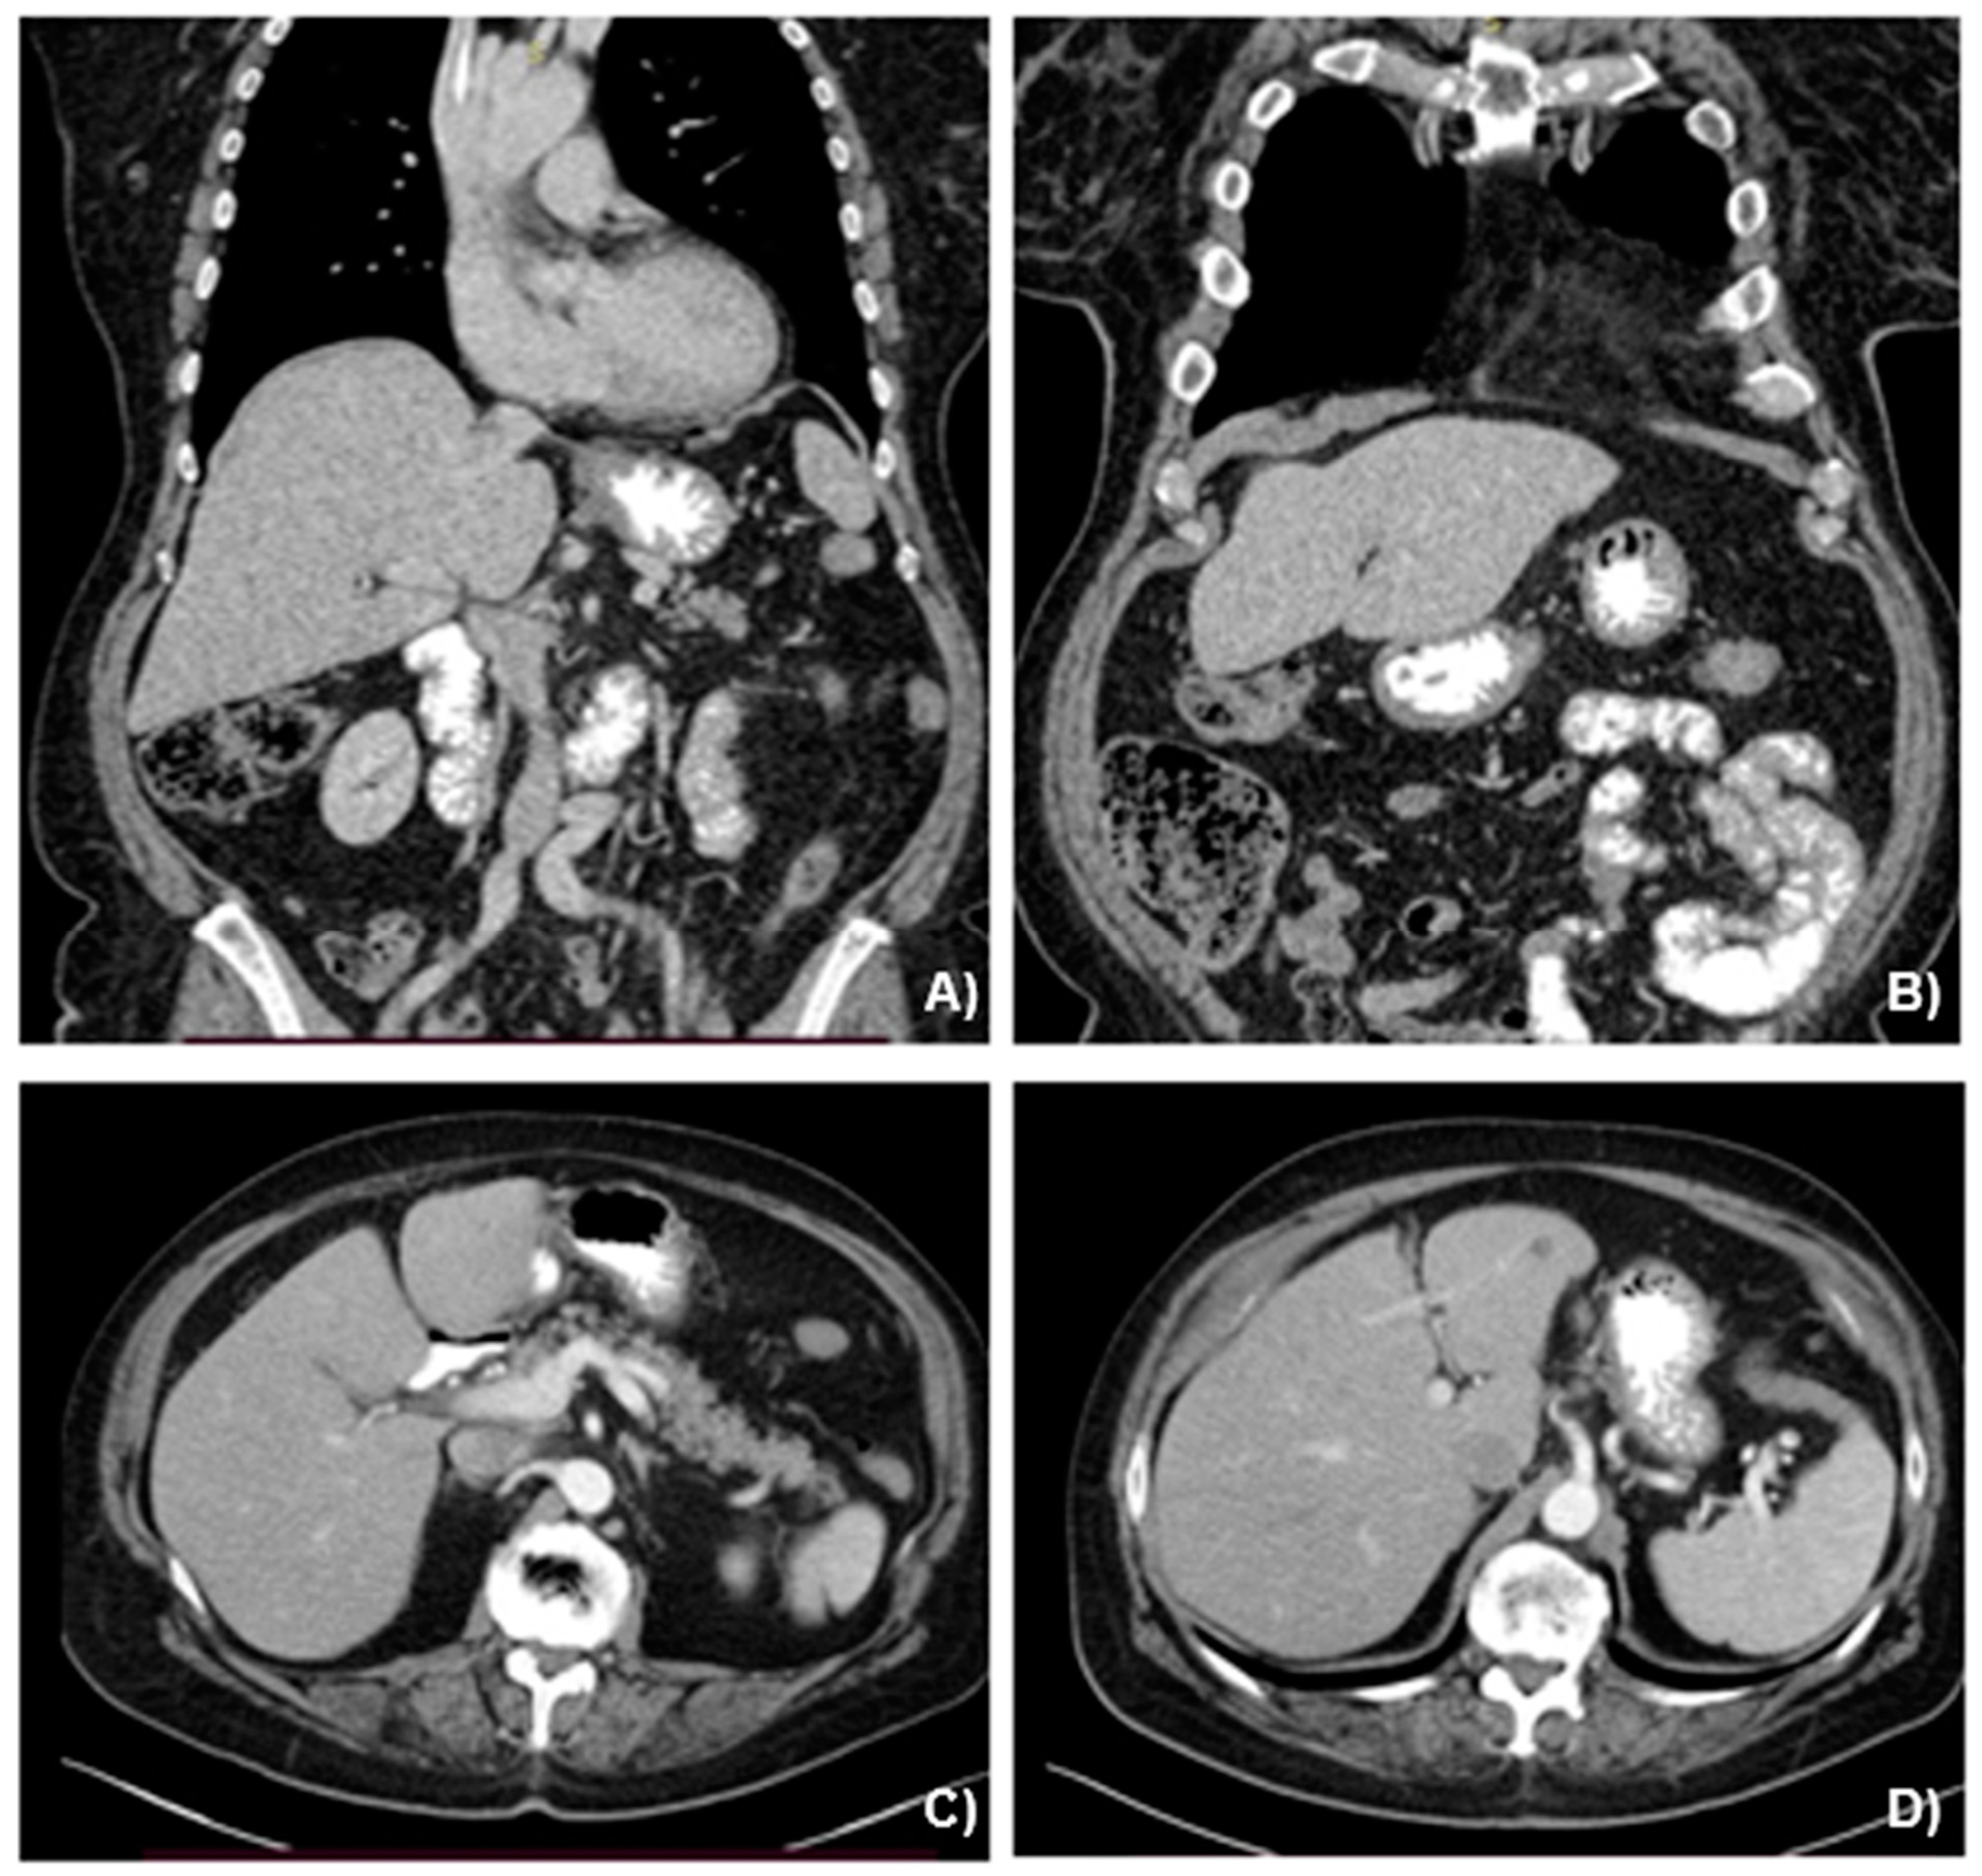

2.2. Case Presentation

3.1. Case Management